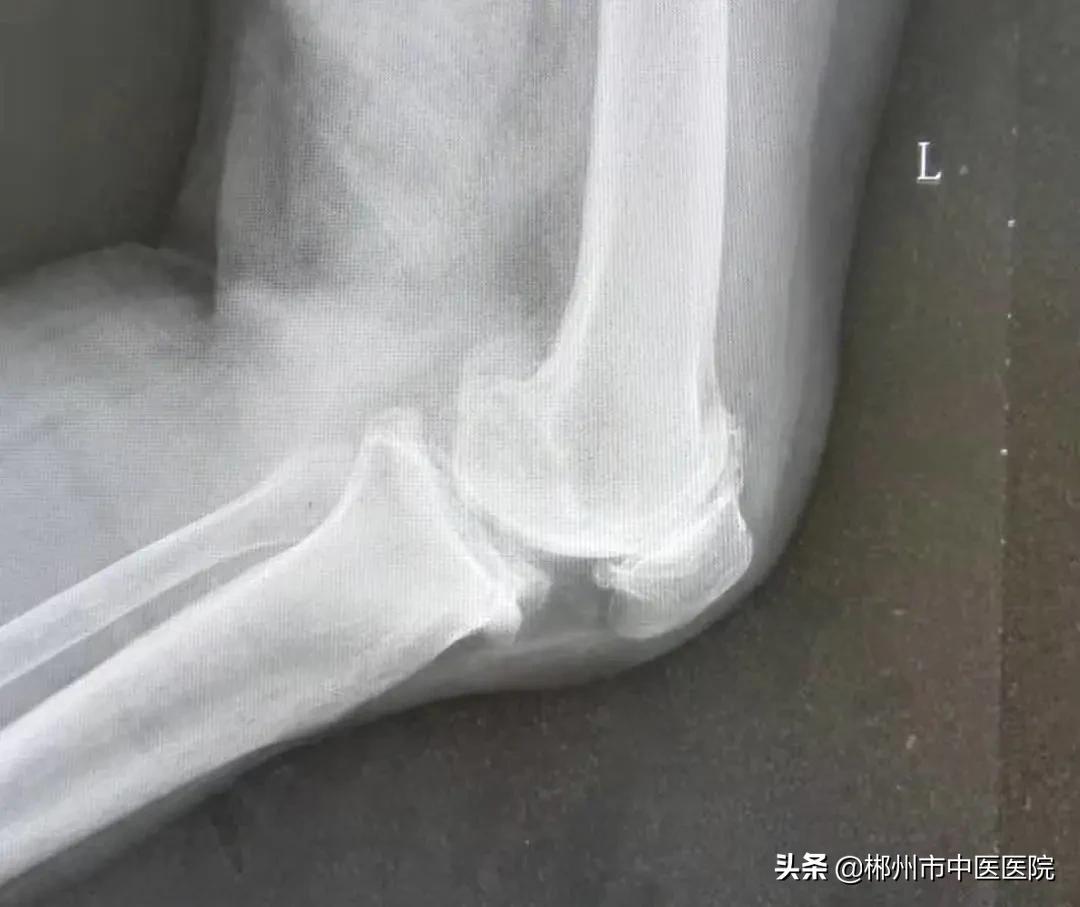

检查后发现李奶奶双膝关节肿胀、内翻畸形,左膝关节特别严重。

治疗前X线片情况